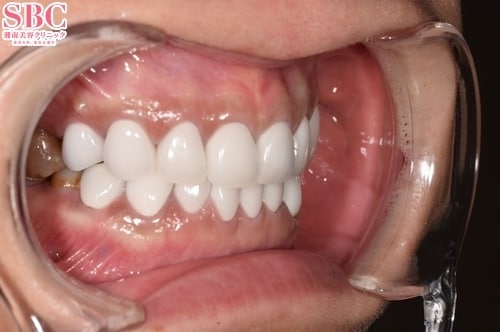

施術後5ヶ月後

術後

上の歯8本、下の歯8本のセラミック治療で、色、形の美しく整った自然な前歯に改善させていただきました♪